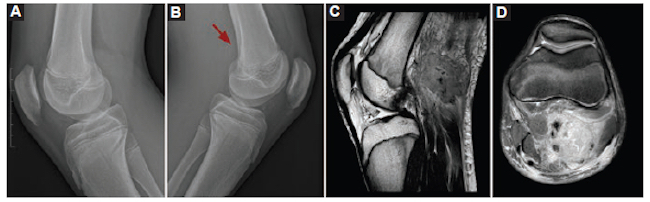

Varón de 16 años que consultó por un cuadro clínico de 3 días de evolución caracterizado por dolor, edema e impotencia funcional en el miembro inferior izquierdo, y fiebre. Como antecedente, había sufrido una caída de su propia altura realizando deporte. Se realizaron Rx y posteriormente RM, la cual informó una masa en el hueco poplíteo de características tumorales. Por su aspecto, el principal diagnóstico considerado fue el de fibromatosis agresiva. Se realizó punción-biopsia guiada por ecografía (Fig. 4).

Durante el procedimiento se evacuó contenido purulento y el resultado de la anatomía patológica informó un proceso inflamatorio agudo por Staphylococcus aureus resistente a la meticilina.